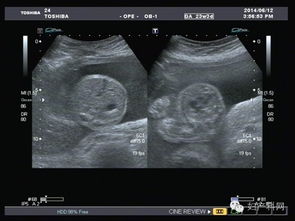

超聲波檢查,通過超聲波檢查出胎寶寶的體重、位置、大小。胎盤位置、羊水?dāng)?shù)量、呼吸運(yùn)動等情況,以便判斷是進(jìn)行自然分娩還是剖腹產(chǎn)

特別是對于月經(jīng)不準(zhǔn)或者記不清楚最后一次月經(jīng)的孕媽媽來說,在懷孕早期可以利用超聲波檢查預(yù)見預(yù)產(chǎn)期。還可以檢查胎兒是否缺氧,或者孕婦是否是宮外孕。但是,超聲波最主要的還是堅(jiān)持寶寶在腹中的生長情況。

現(xiàn)代社會,雖然科技在不斷發(fā)展,但是環(huán)境也在受到更嚴(yán)重的污染,這就導(dǎo)致了許多畸形胎兒的生長,而超聲波檢查就能告訴你胎兒生長是不是正常,是否有什么缺陷,有特別的情況的話,醫(yī)生通過超聲波檢查可以告訴你,比如,有些遺傳病可以在寶寶出生之前檢查出來,比如營養(yǎng)性肌肉發(fā)育不良,如果是男孩的話很容易造成遺傳,這樣的話醫(yī)生會通過檢查結(jié)果告訴你最好不要孩子。

一般來說,在第18周-20周進(jìn)行第一次超聲波檢查。它能大致診斷出胎兒是否畸形,觀察胎兒的活動狀態(tài)。

在懷孕第34周第二次超聲波檢查的目的是監(jiān)測羊水量、胎盤位置、胎盤成熟度及胎兒有無畸形,了解胎兒發(fā)育與孕周是否相符。 最后是在第37周以后,超聲檢查主要目的是確定生產(chǎn)方式,為了監(jiān)測羊水量、胎盤成熟度,必要時(shí)需要每周一次B超。